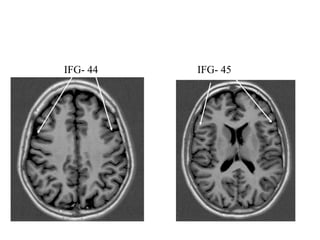

• IFG (44(opercularis) 45(triangularis) 47 (orbitalis)

IFG- 44 IFG- 45

IFG 47 GR OG